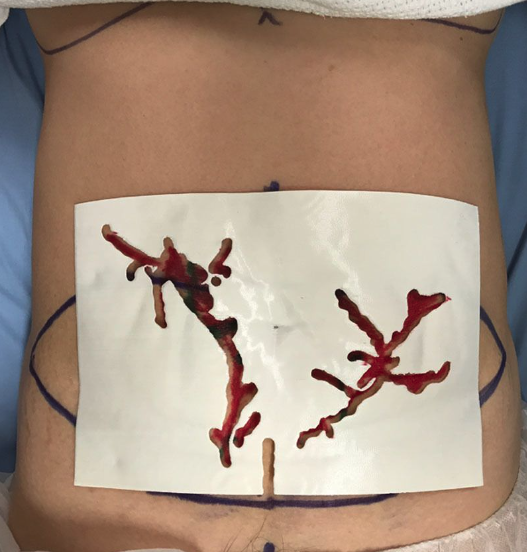

HDU was the first imaging modality used to identify perforators for preoperative flap mapping6 due to its user-friendly function and ability to identify perforators in real time. This handheld instrument allows surgeons to identify single perforating vessels bedside to the patient in a noninvasive modus operandi (Figure 1). To perform this feat, HDU utilizes high-frequency acoustic signaling to measure red blood cell flow, with the largest perforator correlating to the highest density of flow.7 This quality alone contributes to patient comfort (as the patient lies in a supine position during imaging) and a favorable safety profile (due to its lack of radiation).